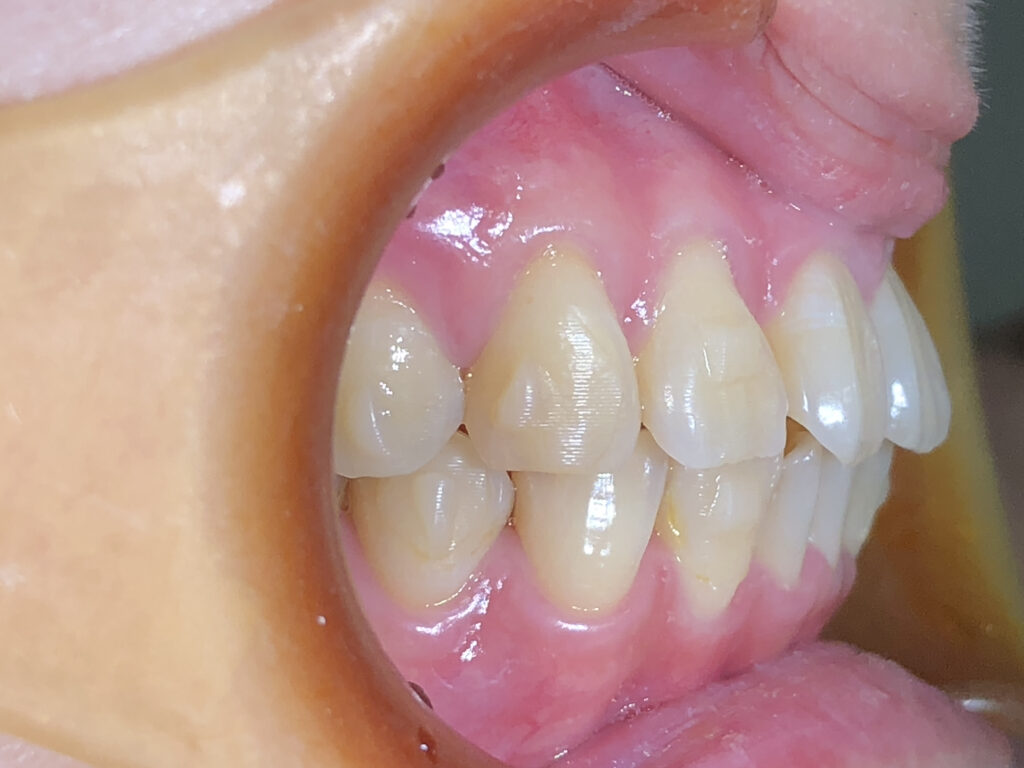

右側

治療前

治療後